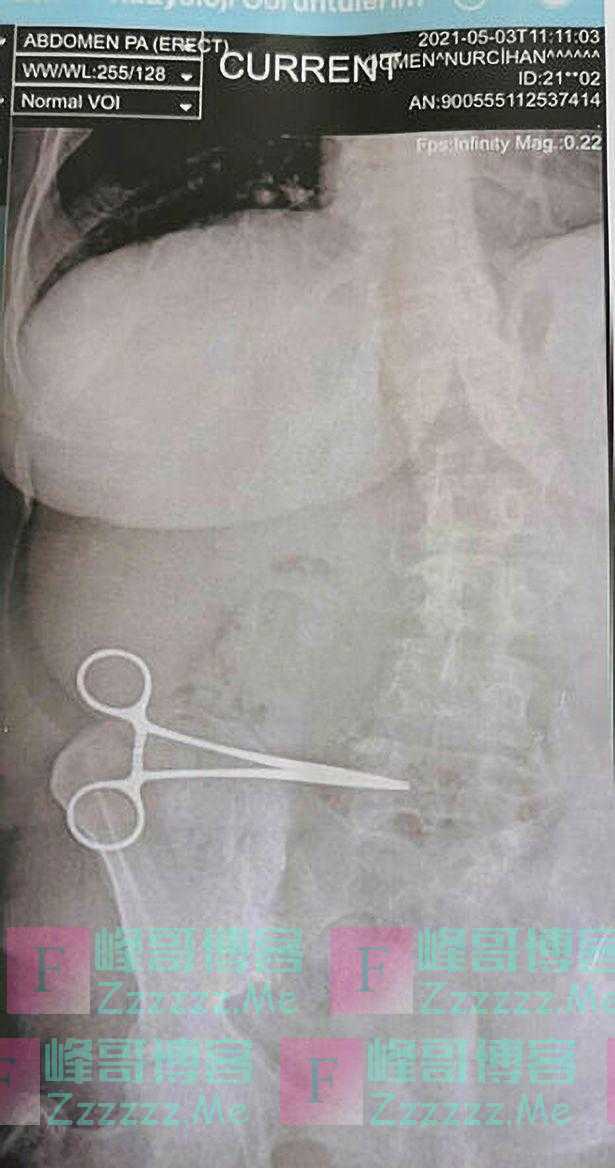

这种症状一直持续了两个月时间,努尔齐汉后来和她的丈夫去了一家州立医院,X光片显示努尔齐汉的腹部内有一把剪刀。之后,努尔齐汉又去找了那名外科医生,后者通过两个小时的手术取出了那把剪刀。